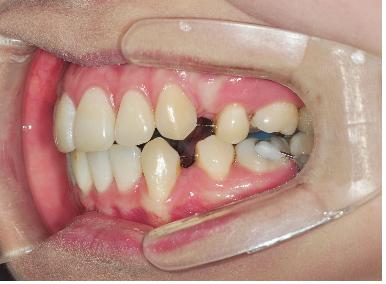

이번 월치료에는 와이어교체와 훅부착하였습니다.

와이어를 약간 더 굵은 걸로 교체하였는데요 ,

와이어가 굵어서 그런지 브라켓이 잘 안 닫겨 선생님들께서 고생하셨는데요ㅠㅠ

닫기기는 하나 와이어의 굵기에 못 이겨 다시 열릴까바 염려하셔서

열릴 꺼 같은 브라켓에는 철사로 묶어주셨어요ㅠㅠ

선생님과 치위생사언니 고생이 너무 많으셨어요 (꾸벅꾸벅!)